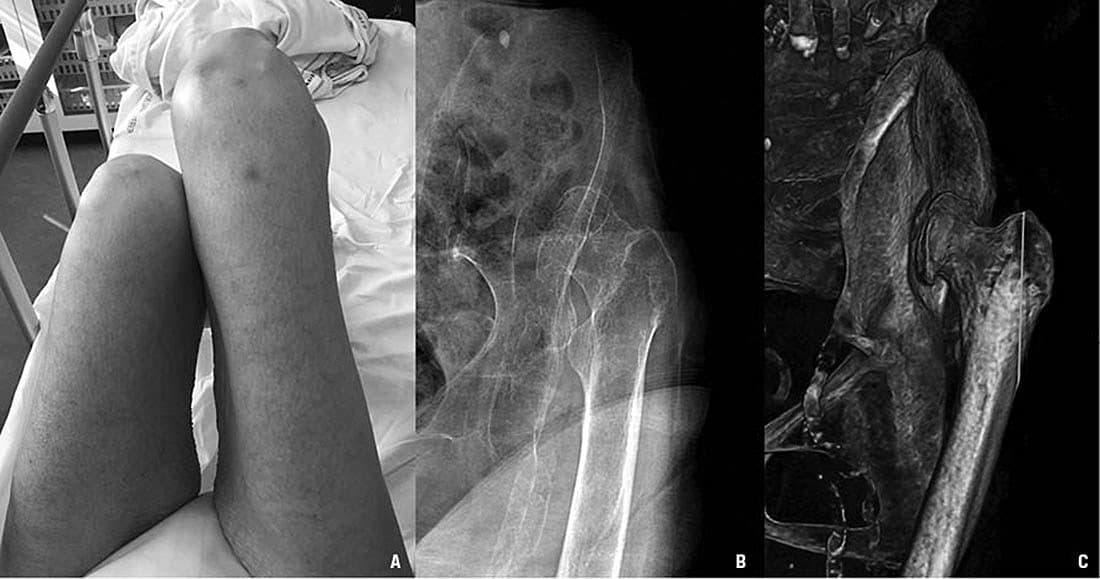

En 83-årig dement, kvindelig plejehjemsbeboer blev fundet siddende på gulvet og var vanskelig at mobilisere. Vagtlægen havde mistanke om et hoftenært knoglebrud og henviste patienten til skadestuen. Den objektive undersøgelse viste et forkortet venstre ben uden udadrotation (A), ingen ømhed og næsten normalt bevægeomfang. Røntgenundersøgelse og CT viste en kronisk lukseret, dysplastisk hofte med caputnekrose og dannelse af et falsk hofteled (B, C). Den praktiserende læge og de pårørende kunne efterfølgende oplyse, at patienten altid havde haltet, men aldrig var blevet udredt herfor.

Kronisk hofteluksation med dannelse af et falsk hofteled er en tidligere velkendt, men nu sjælden komplikation i forbindelse med ubehandlet hoftedysplasi. Kronisk hofteluksation kan være symptomfattig, men ofte er der smerter og slidgigt i hofte eller knæ [1]. Hoftedysplasi forekommer hos 1-28 pr. 1.000 børn, overvejende piger, og i ca. 20% af tilfældene på begge sider [2]. Risikofaktorer er fødsel i sædestilling, førstegradsslægtning med hoftedysplasi og positiv dislokationstest, som bør medføre udredning [2-4]. Konservativ og operativ behandling er effektiv og har næsten udryddet denne nu sjældne komplikation.